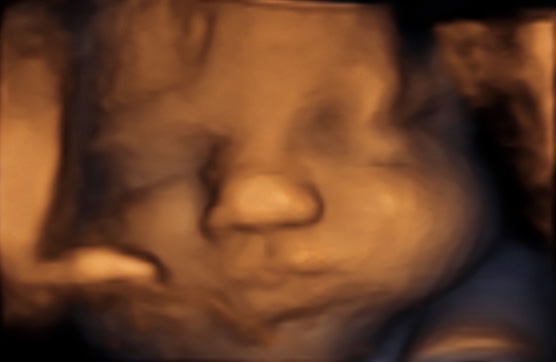

34 weken